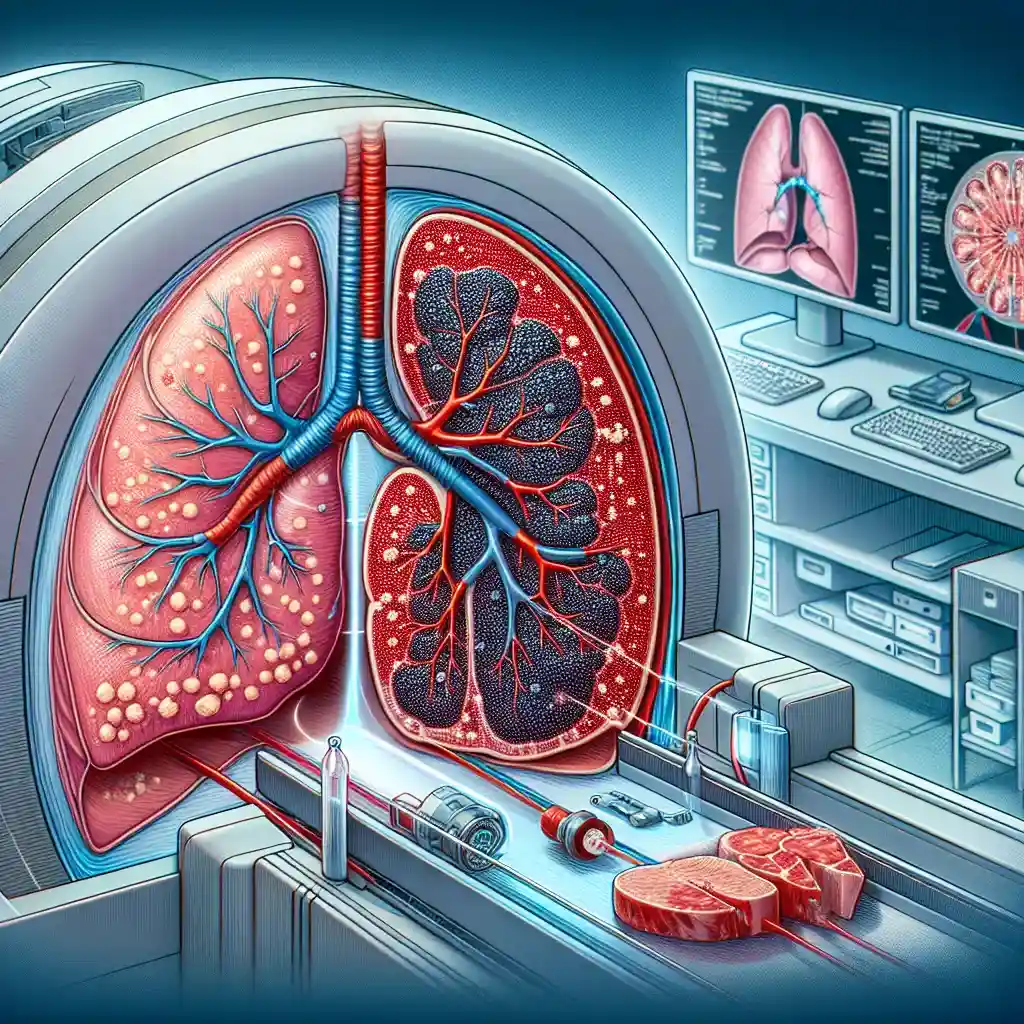

Метод компьютерной томографии (КТ) легких является одним из самых современных и точных методов диагностики заболеваний дыхательной системы. Используя высокоточную технологию, врачи могут получить послойные изображения легочной ткани, что позволяет обнаружить даже мельчайшие патологии на ранних стадиях. В ведущих клиниках Украины, таких как в Киеве и Одессе, этот метод успешно применяется для раннего выявления воспалительных процессов, опухолевых образований и других нарушений. Если вы заботитесь о своем здоровье, не откладывайте обследование – своевременная диагностика может спасти жизнь.